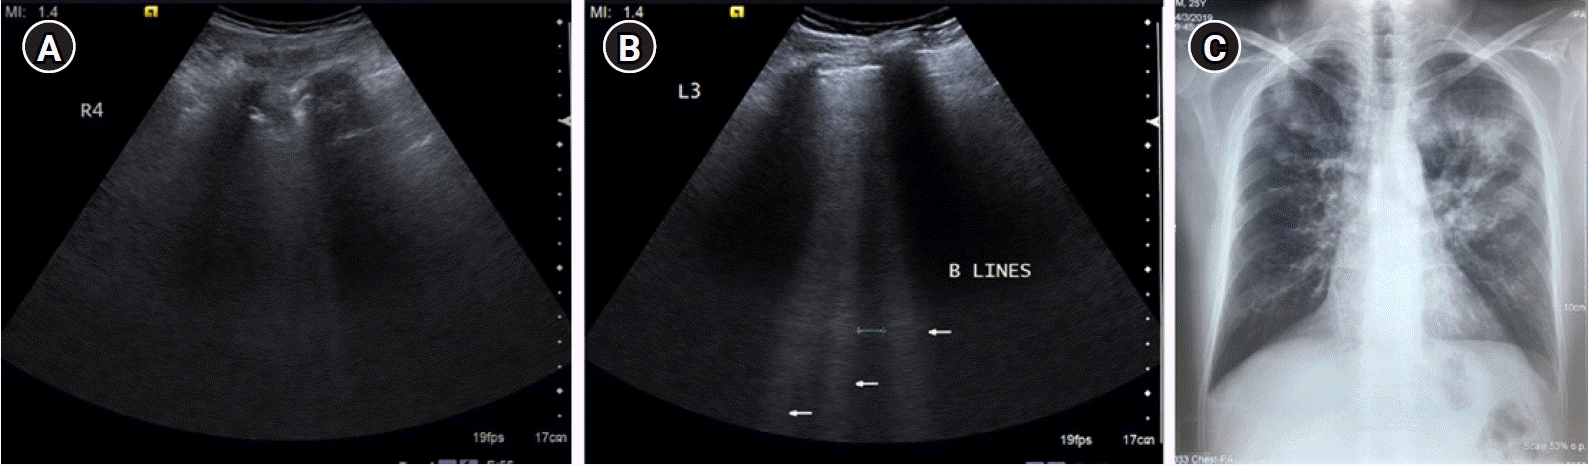

Figure 8.

(A) Longitudinal scan of anterior chest wall showing 3 “B-lines”: comet-tail artifacts, always arising from the pleural line, and always moving in synchrony with lung-sliding. They are almost always long, well-defined, laser-like, hyperechoic, erasing A-lines, and are considered significant when ≥3. Few B-lines may be normally seen in basal lung zones. (B) Cine US clip demonstrating the same (Supplementary Material 3).

The presence of three or more B-lines in one longitudinal scan, disseminated to the anterior chest wall bilaterally with preserved lung sliding is called the B-profile. One must carefully assess a vertical artifact before calling it a B-line. The following are the features of a B-lines (Figure 8) as described by Lichtenstein [7]: (1) B-line is a comet tail artifact. (2) It always arises from the pleural line. (3) Always moves in synchrony with lung sliding. (4) Almost always long, spreading out without fading to edge of the screen. (5) Almost always erases A-lines. (6) Almost always hyperechoic.